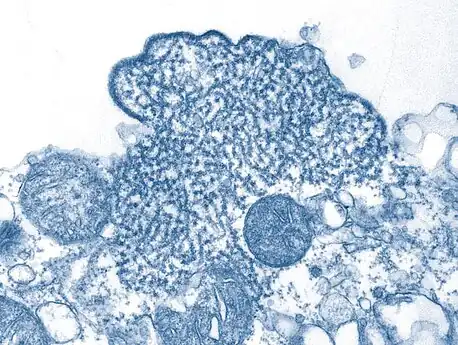

False-color electron micrograph showing a Nipah virus particle (purple) by an infected Vero cell (brown)